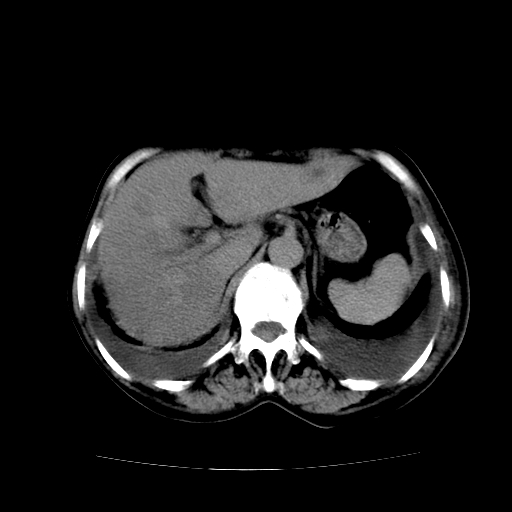

女70y乳腺ca(针吸活检)

多部位转移瘤的诊断可以肯定,我的疑问是:双肺对称高密度影及胸水是否为心衰肺水肿,病人体虚弱,不好意思图象传的乱![em9]

肺部病变为淋巴转移,肝脏转移,及局部淋巴转移。胸水可能为淋巴回流受阻(血性的考虑胸膜转移)

癌性淋巴管炎,肝脏转移,瓷胆囊

1)左侧乳腺癌并左侧腋窝及纵隔淋巴结转移,两肺淋巴道转移(癌性淋巴管炎),肝脏多发性转移。2)双侧胸腔积液。3)慢性胆囊炎。